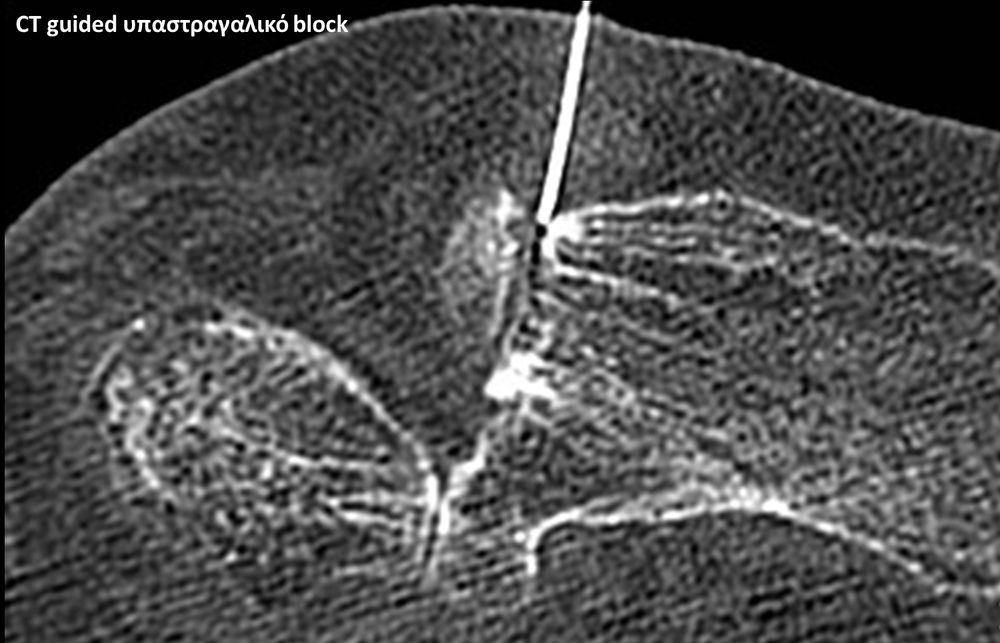

Με την βοήθεια της επεμβατικής ακτινολογίας είναι δυνατόν να πραγματοποιηθούν διαφορες ενέσιμες τεχνικές που αποσκοπούν στη μείωση του μυοσκελετικού πόνου, την ενίσχυση της αποτελεσματικότητας της φυσιοθεραπείας και την επιτάχυνση της διαδικασίας επούλωσης. Οι τεχνικές αυτές περιλαμβάνουν την κατευθυνόμενη έγχυση φαρμάκων ή πραγματοποίηση θεραπευτικών χειρισμών ακριβώς στη θέση τηςπαθολογία. Ετσι εξασφαλιζεται η μέγιστη αποτελεσματικότητα ( έως 95% κατά περίπτωση) και ασφάλεια σε σχέση με τυφλούς χειρισμούς χωρίς ακτινολογική καθοδήγηση.